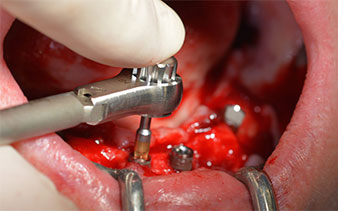

Zunächst wurde das Foramen mentale als limitierende anatomische Struktur dargestellt und die krestale Kortikalis mit dem geraden Handstück und einem großen Rosenbohrer geglättet (Abb. 4).

Das chirurgische Protokoll der verwendeten Implantate (SKY, bredent medical) schreibt eine Umdrehungszahl von 1.200/min für die Pilotbohrungen vor (Abb. 7–9).

Dies entspricht der nächsten Position der Voreinstellung am Implantmed. Zu erkennen ist die etwa 45-Grad-Schräghaltung des W&H Winkelstückes nach mesiokaudal in Regio 45, um den Nervus mentalis zu schonen. Das Foramen mentale gilt als anatomische Orientierung für alle Bohrungen in diesem Bereich. Die anschließenden Bohrungen werden mit einer reduzierten Umdrehungszahl von 300/min durchgeführt (Abb. 10 und 11).